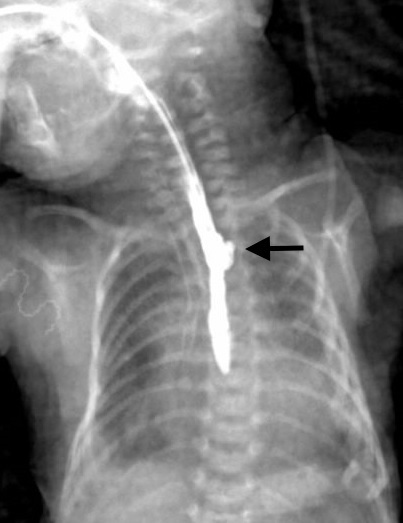

Figure 1

Case 1: The babygram shows the tip of the naso-esophageal tube at the level of the 7th thoracic vertebra. Hyperlucency around the tube mimics the upper esophageal pouch (arrow). The presence of air in the stomach/bowel loops is noted.